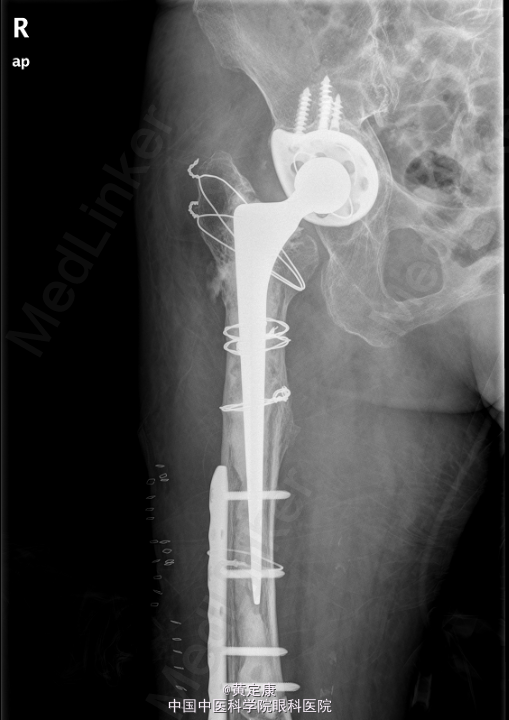

患者,女,82岁,因“摔伤致右下肢疼痛伴功能受限1天”入院。 患者1天前因外伤致右下肢剧烈疼痛,无法行走,。送至外院急诊,X线示“右股骨髁上骨折”,拟“右股骨髁上骨折”收治入院。

右膝部肿胀,膝关节活动受限,右足各趾活动感觉正常,末梢血运正常。石膏固定。检查提示:右股骨髁上骨折。

初步诊断: 右股骨髁上骨折 行[右]股骨骨折切开复位钢板内固定术